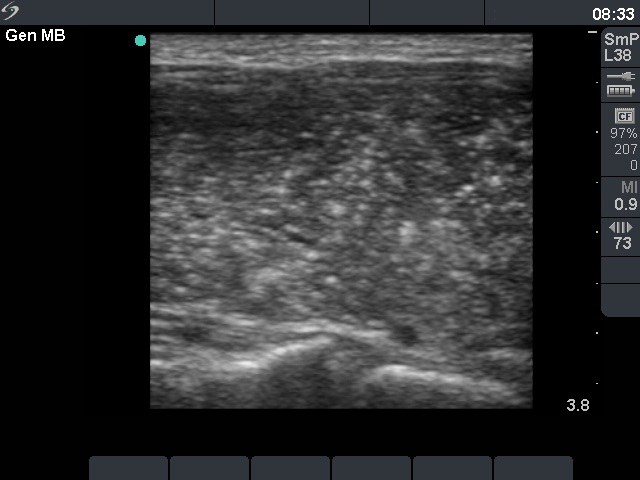

Follow-up examination 17 months after first visit (second and third rows):

Clinical presentation: The patient was well. She came to sonographic follow-up suggested at her first visit.

Palpation: a hard nodule in the upper part of the left thyroid.

Functional state: subclinical hyperthyroidism (TSH undetectable, FT4 21.1 pM/L, FT3 6.68 pM/L).

Ultrasonography: The echogenicity index of the thyroid was 50%. The vascularization was not significantly increased. There was a large hypoechogenic, inhomogeneous nodule in the upper part of the left lobe. Both the intranodular and the perinodular blood flows were increased.